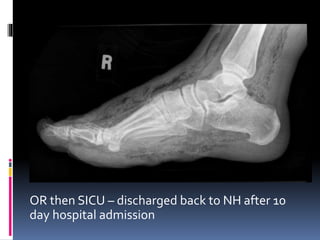

 XRAY?

OR then SICU – discharged back to NH after 10

day hospital admission

Management  Resus bay– Sepsis bundle, large bore IVs, 30 ml/kg fluid bolus  Required norepinephrine (initiated at 10 mcg/min) to maintain a MAP > 65 mm Hg  XRAY?

OR then SICU– discharged back to NH after 10 day hospital admission